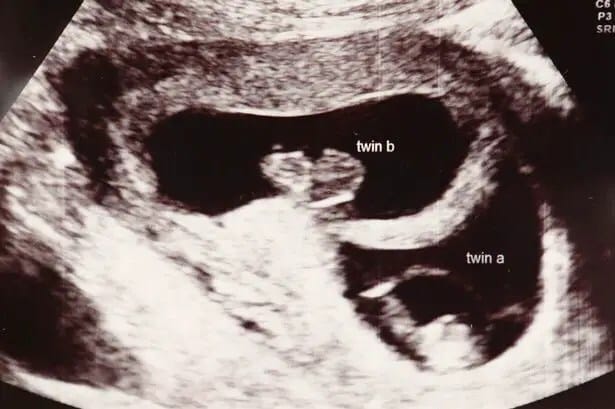

Cuando Maria Jones- Elliot abraza a sus dos bebés, las nombra como sus «pequeños milagros». Es que los niñas, Amy and Katie, nacieron con 87 días de diferencia.

María primero dio a luz a Amy, pero Katie nació tres meses después. Los increíbles nacimientos llegaron al Record Guinness por el mayor intervalo en el nacimiento de gemelos. El record registrado era de 84 días.

Finalmente, Amy nació a las 24 semanas de gestación, cuatro meses antes de la fecha estimada, era muy pequeña y fue internada en cuidados intensivos. Luego de cinco semanas le permitieron tomarla en brazos y cada día colocaba a la pequeña sobre su panza para que sintiera a su hermana. Cada día que pasaba era un bonus para Katie, quien iba creciendo fuerte dentro del veintre.

Finalmente, a las 36 semanas nació la segunda niña en perfecto estado. Dos horas después la colocaron en la incubadora juntas y Amy le sonrió, «no hay dudas de que se reconocieron mutuamente», sostuvo la mujer.